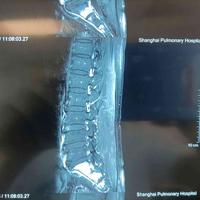

强直性脊柱炎

查看图片需登陆

强直性脊柱炎...

由 medjpg 发表于 2026-03-24 22:32